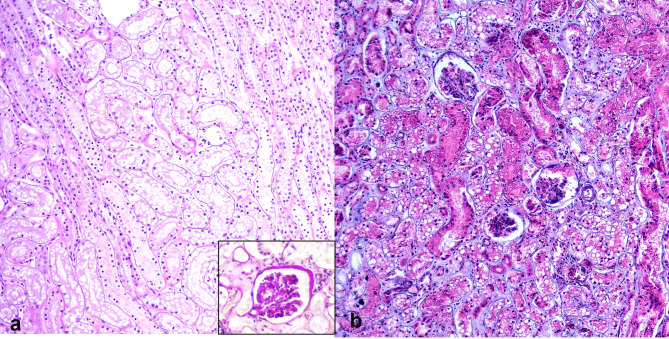

Methods: Kidney tissues from 150 deceased cats with suspected or confirmed chronic kidney disease (CKD) were screened for FeMV using conventional reverse-transcription PCR (cRT-PCR). Positive cases were genotyped and quantified for viral load using reverse-transcription digital PCR (RT-dPCR). A control group of nine FeMV-negative kidneys with CKD was included for comparison. Histological evaluation was conducted using hematoxylin and eosin (H&E), periodic acid-Schiff (PAS), and Masson's trichrome staining. Immunohistochemistry (IHC) and in situ hybridization (ISH) were employed to localize viral antigens and assess expression of apoptotic markers, including cleaved caspase-3 (cCasp3), B-cell lymphoma 2 (BCL-2), and BCL-2-associated X protein (BAX).

Results: FeMV RNA was detected in 6% (9/150) of kidneys, all classified as genotype 1. Histological findings in FeMV-positive cases included eosinophilic intracytoplasmic inclusion bodies, lymphoplasmacytic tubulointerstitial nephritis (TIN) and varying degrees of fibrosis. FeMV antigens were localized in the renal tubular epithelial cells. Statistically, cCasp3 expression (P = 0.005) and interstitial fibrosis (P = 0.040) were significantly higher in FeMV-positive cases than in FeMV-negative controls. No significant differences were observed for TIN, BAX, or BCL-2 expression (P > 0.05). Among FeMV-positive cases, viral load was significantly associated with cCasp3 expression (P = 0.049), but not with TIN, fibrosis, BAX, or BCL-2 expression. Spearman's correlation revealed a strong positive correlation between viral load and cCasp3 expression (ρ = 0.8222, P = 0.007).